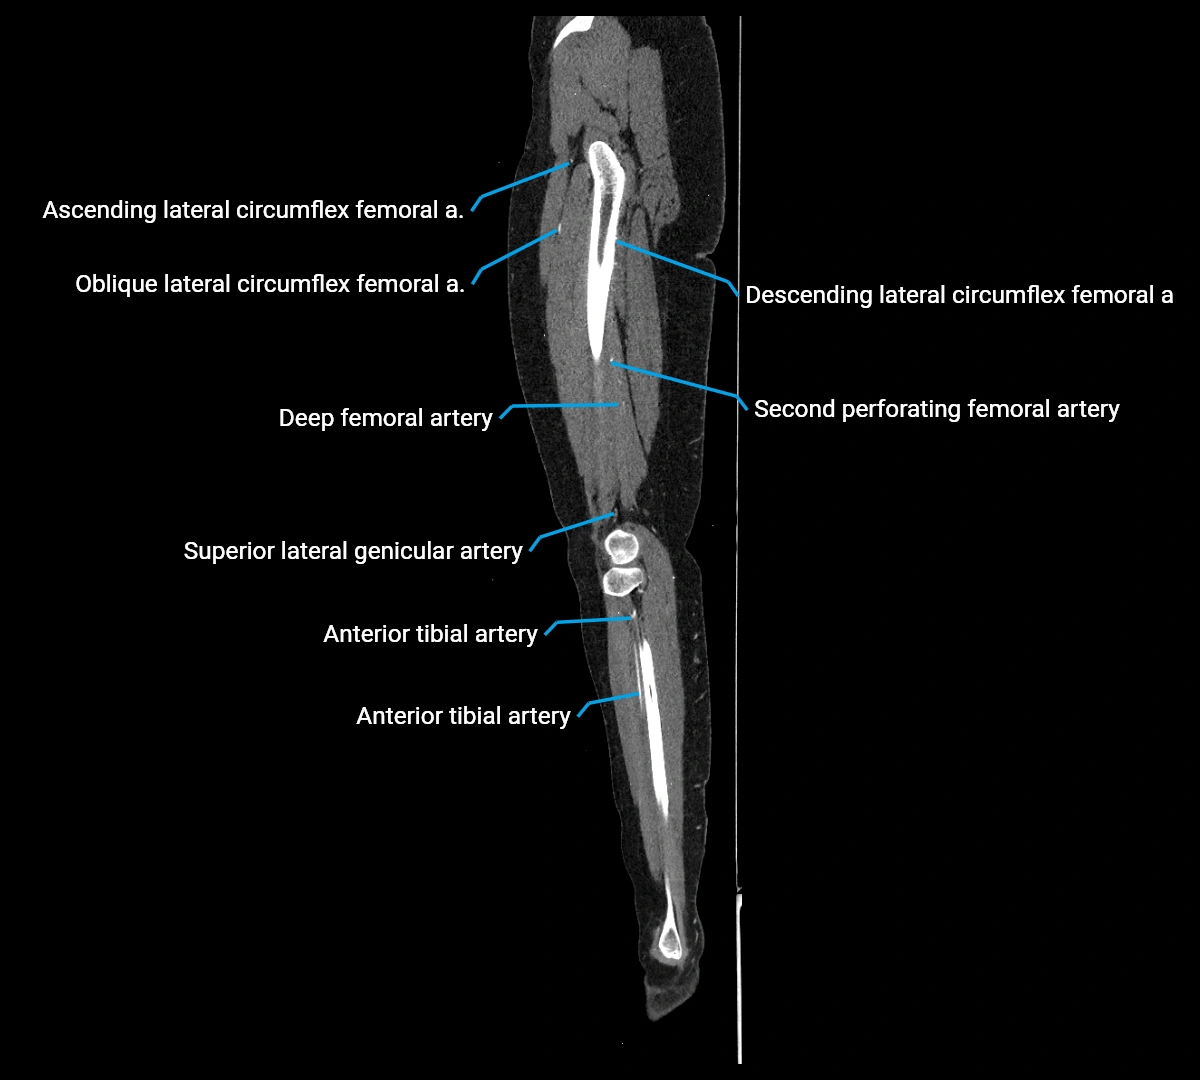

Contrast-enhanced CT (CTA):

• Gold standard for abdominal aortic imaging

• Provides excellent detail of lumen, wall, aneurysm, thrombus, and branch vessels

• Multiplanar and 3D reconstructions help in aneurysm measurement, stent graft planning, and dissection evaluation

• Detects acute rupture, traumatic injury, or occlusion with high sensitivity